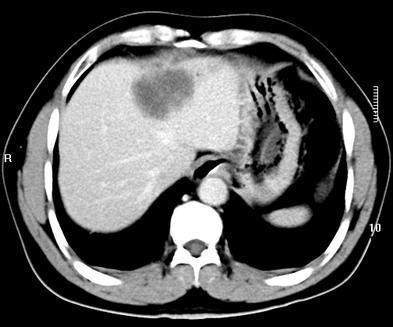

标题: CT19720:肝右叶血管瘤。肝左叶内侧段病灶考虑什么? [打印本页]

标题: CT19720:肝右叶血管瘤。肝左叶内侧段病灶考虑什么?

男,48岁,肝区不适月余,伴隐痛。

支持右叶血管瘤,左叶病灶考虑肝腺瘤。

1)不排除肝左叶肝癌。2)肝右叶血管瘤。

肝左叶炎性病变,肝癌待排。2)肝右叶血管瘤。

1.肝右叶血管瘤;2.肝左叶炎性假瘤?肝癌?建议穿刺活检.

右叶病灶典型,左叶病变慢性炎块

1、肝右叶血管瘤(典型)。

2、肝左叶病灶,强化不明显,疑炎性假瘤,建议结合临床并密切随访。

1、肝左叶炎性病变,肝癌待排。

2、肝右叶血管瘤。

肝左叶脓肿,肝癌待排。2)肝右叶血管瘤